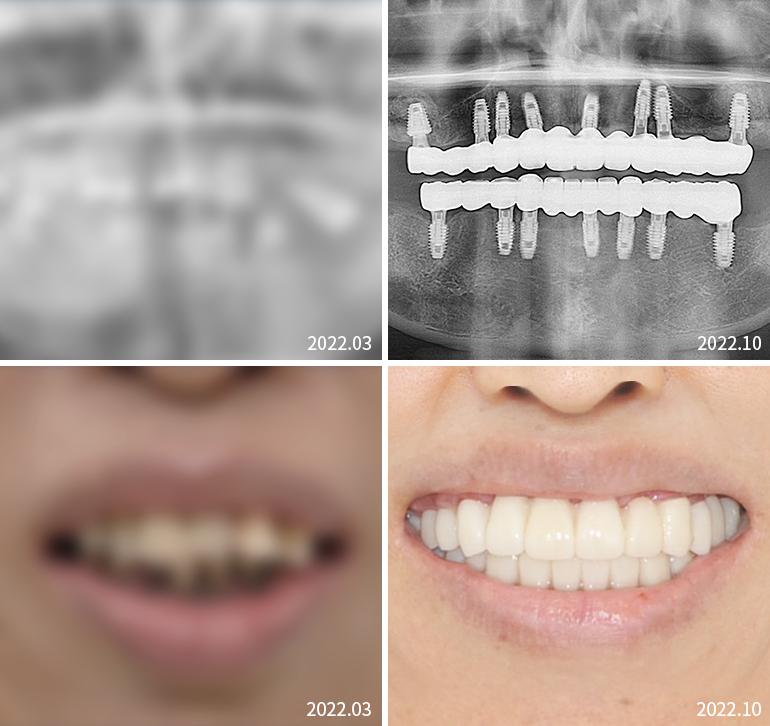

전체임플란트